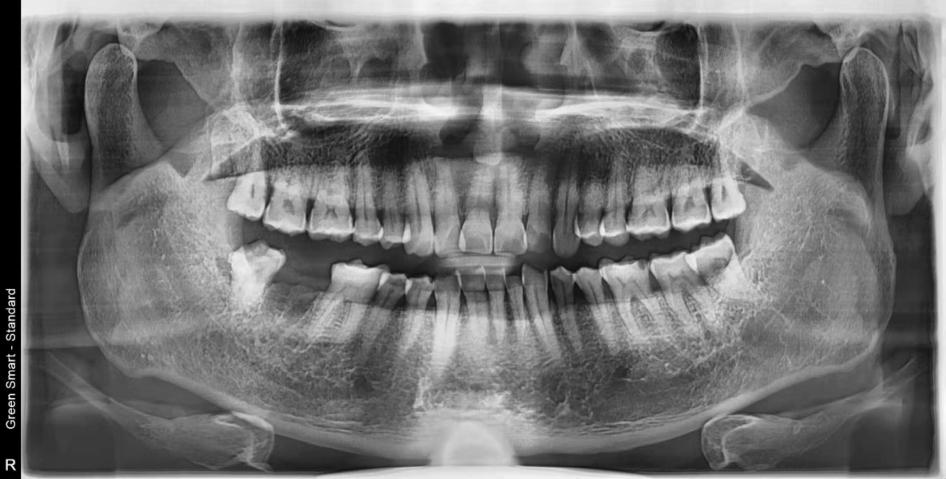

種植牙後:

深圳維港口腔謝立華醫生,目前為深圳業界知名的種植牙醫生,對於微創無疼植牙及即刻負重植牙,有著極為精湛的技術和豐富臨床經驗。好多香港朋友會過來找謝立華醫生進行植牙修復,顧客評價“手勢好,專業”。